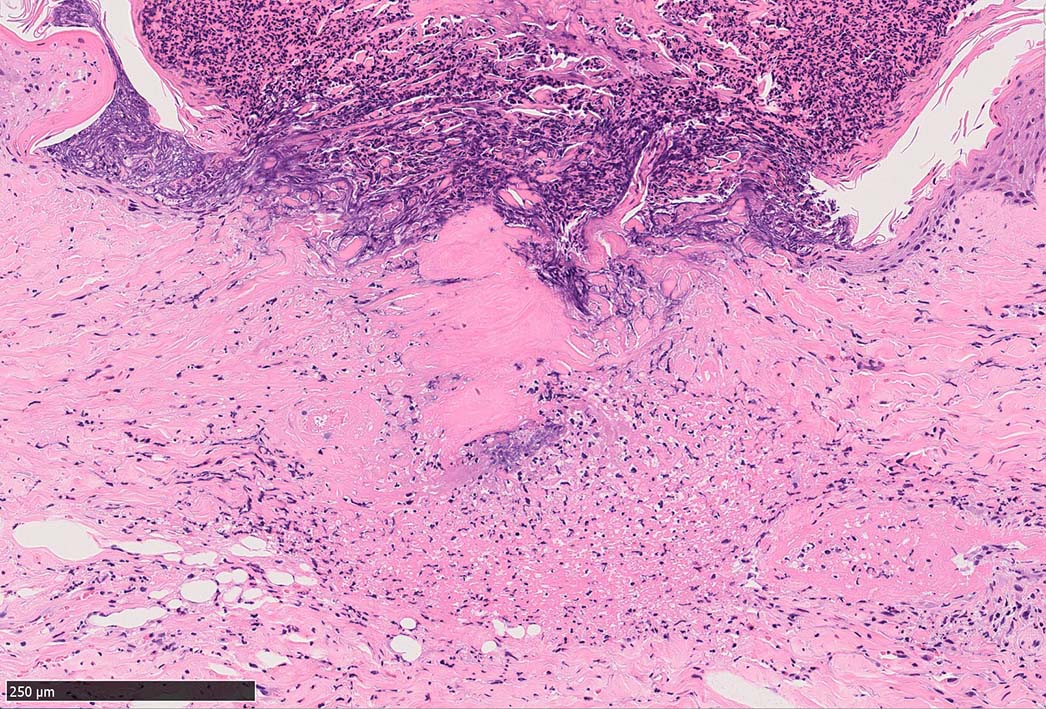

痂皮の下に硝子様凝固物があり, 周囲には壊死組織が形成されている. 近傍の細血管には凝固物による閉塞の所見があるように見える. 連続する細血管には, fibrinoid necrosisを呈する壊死性血管炎が認められる.